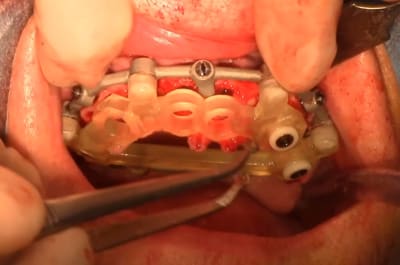

Vous avez constatés que dans ma conception des guides le support osseux est privilégié.

3 raisons principale, il me semble impératif de préparer le support osseux avant de poser et j'ai pu observer dans des cas d'édentations qui ont plusieurs années des tissus fibreux sont à retirer, la levée du lambeau permet de réaménager les tissus et obtenir la laxité du conjonctif pour recouvrir les ROG.

Le flapless me semble plus un argument pour donner illusion que l'implantologie peu s'affranchir de faire de la chirurgie.

Le positionnement osseux donne toute la liberté de planifier librement les réhabilitations globales.

Un exemple d'un cas plébiscité pourtant lacunaire

j'y vois des greffes de sinus en vu d'une MCI se qui implique environ 6 mois d'attente avec un antago précaire.

30/06/2022 à 09h06

la conservation des dents résiduelles pour positionner le guide conduit à une répartition non équilibrée des implants

30/06/2022 à 19h20

Ce qui est prévu 9 implants

résultat, seul 6 implants mis en charge